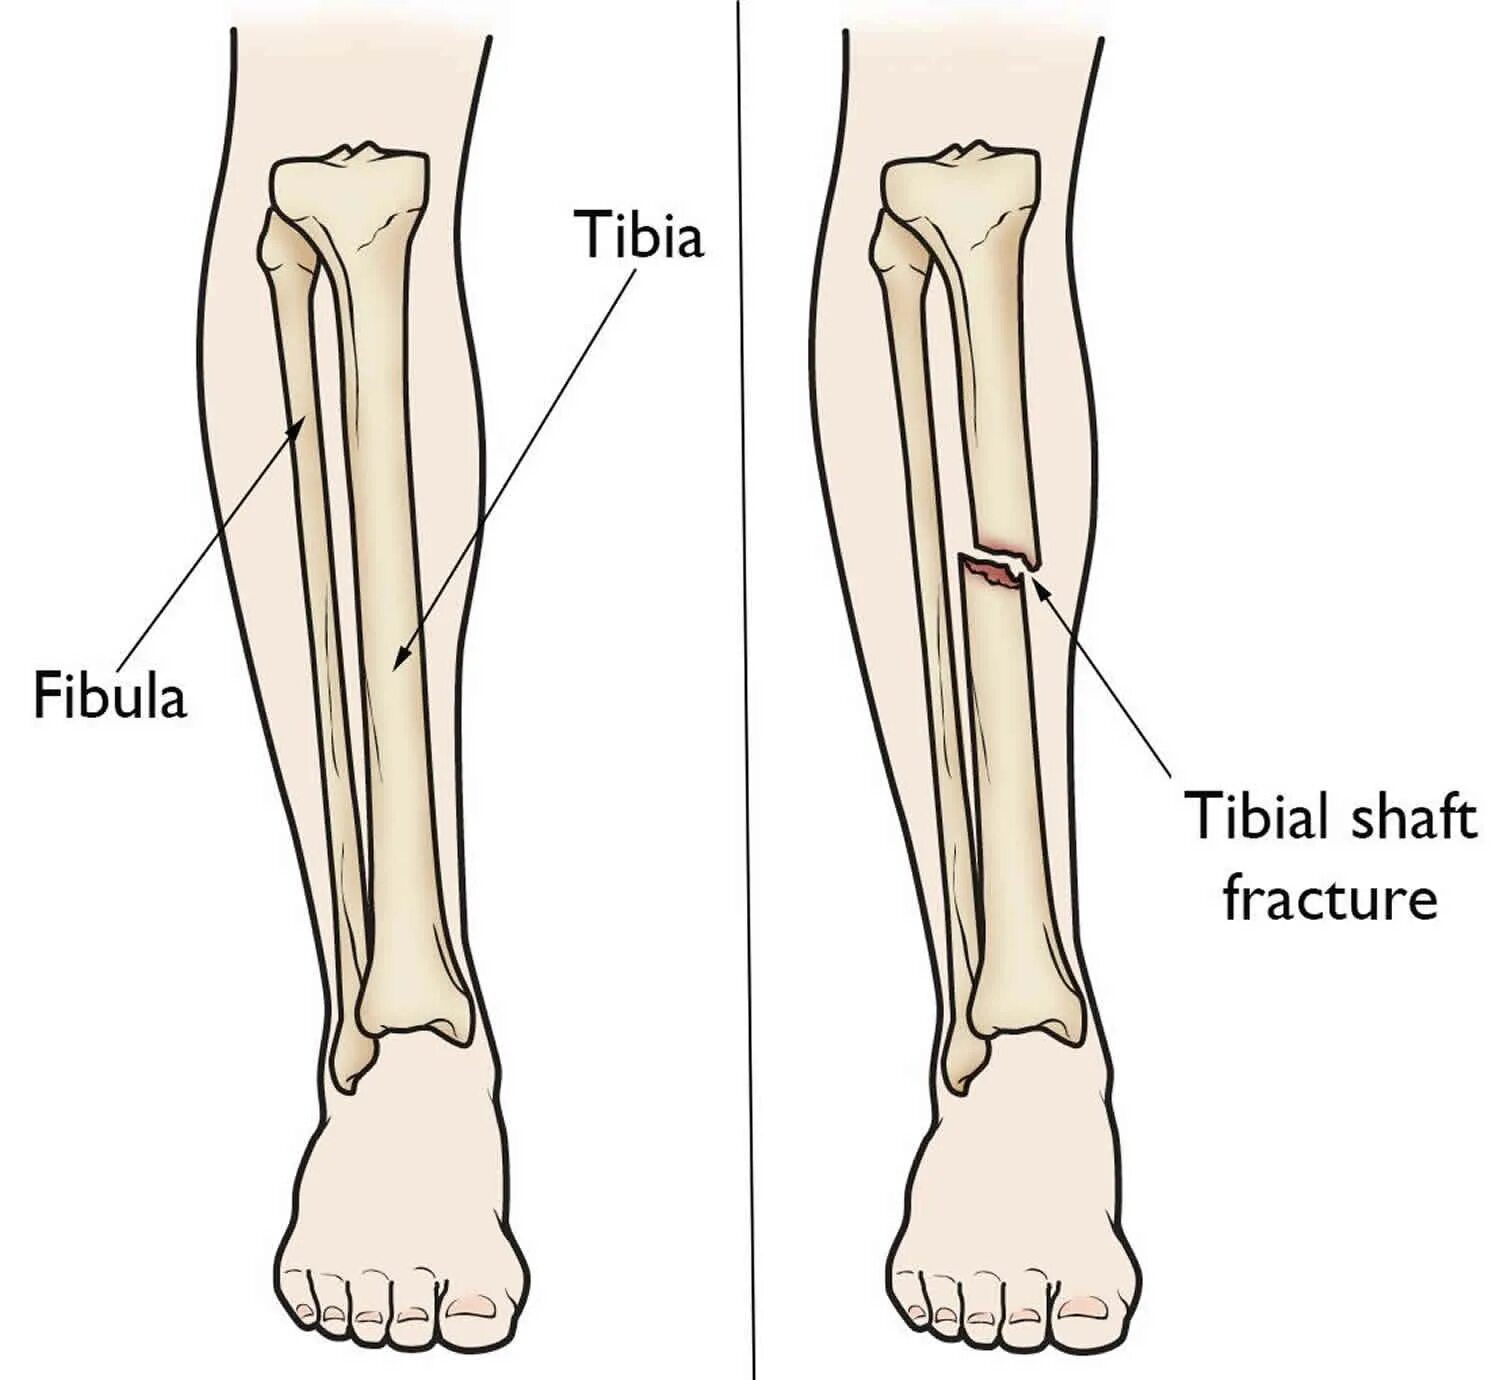

Сколько срастается стопа